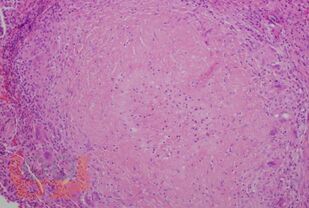

Current data on tuberculosis of orofacial localization are presented. Issues of etiology, classification, pathogenesis, risk factors, clinical features, diagnosis, differential diagnosis are disclosed. An algorithm is presented for examining patients with suspected orofacial tuberculosis and features of the treatment of the disease

In view of the rare localization of the disease, the training material is illustrated by the clinical data of patients with verified orofacial tuberculosis, which are publicly available and published on the Internet in specialized journals.